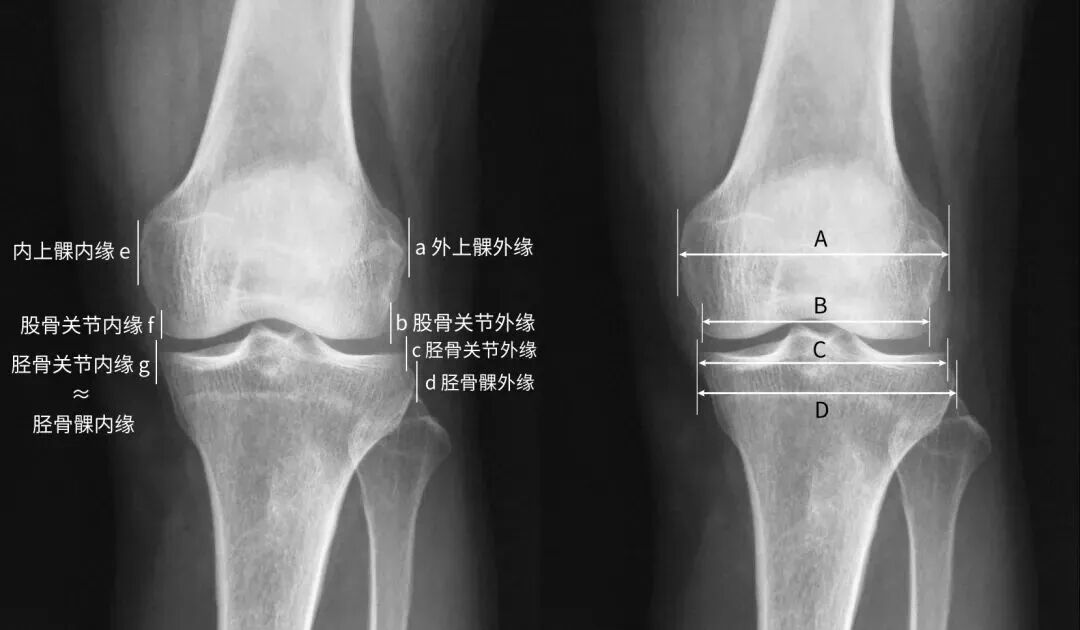

胫骨平台宽度是膝关节正位片上胫骨近端关节面内缘至其外缘的距离。伴 有外侧平台关节面塌陷的胫骨平台骨折常伴有平台增宽,随着关节面复位,平台宽度大多恢复正常。 因此,平台宽度也成为评估关节面复位质量的间接指标,并与患者长期预后相关。

如果关节面复位良好,单纯胫骨平台增宽5~10mm对膝关节功能的影响并不明显因素 ,也不是未来膝关节置换的独立危险因素。